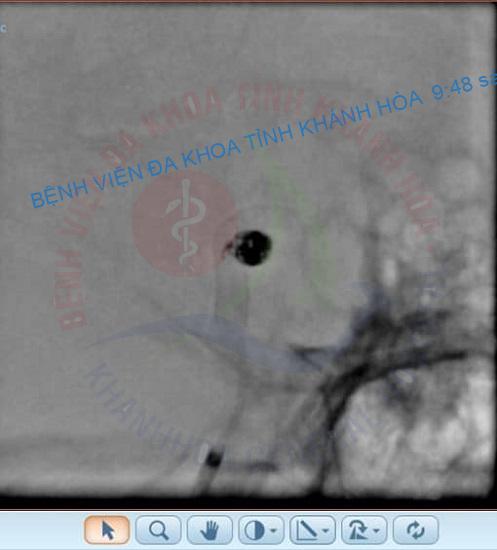

Đánh giá đây là một trường hợp khó, nguy cơ cao và là cấp cứu ngoại khoa, bệnh nhân đã được tiến hành điều trị bằng can thiệp nội mạch làm tắc túi phình. Thủ thuật này được thực hiện bởi các bác sĩ Khoa Ngoại Thần kinh – Bệnh viện Đa khoa tỉnh Khánh Hoà với sự hỗ trợ chuyên môn từ Bác sĩ Trần Quốc Tuấn – Trưởng Đơn vị Can thiệp Nội mạch Thần kinh, Bệnh viện Đại học Y Dược Thành phố Hồ Chí Minh. Sau 3 giờ với kỹ thuật đặt stent đổi hướng dòng chảy (flow diverted) và coiling bảo vệ đáy túi phình, tình trạng bệnh nhân dần ổn định và được xuất viện.

Bác sĩ chuyên khoa II Nguyễn Minh Phước, Trưởng Khoa Ngoại Thần kinh cho biết: túi phình dạng bọng nước là loại túi phình hiếm gặp chiếm 0,3 – 1% túi phình nội sọ và 0,9 – 6,5% túi phình nội sọ vỡ. Dạng túi phình này được mô tả bởi tính chất thành mỏng ở đáy, khó nhận diện cổ một cách rõ ràng và có nguy cơ vỡ cao. Không giống như các túi phình dạng túi, túi phình blister điển hình xuất phát từ phần không phân nhánh thuộc đoạn trên mấu giường (supraclinoid) của động mạch cảnh trong. Điều trị túi phình này là một thách thức lớn khi coiling đơn thuần sẽ rất dễ thất bại, do đó điều trị bằng stent chuyển dòng được coi là lựa chọn tối ưu hơn mặc dù chi phí điều trị cao và bệnh nhân phải dùng thuốc kháng tiểu cầu trong thời gian dài. Khoa Ngoại Thần kinh với đội ngũ bác sĩ được đào tạo bài bản cùng với trang thiết bị hiện đại và sự hỗ trợ chuyên môn của các bệnh viện tuyến trên đang dần làm chủ các kỹ thuật cao, đáp ứng điều trị cho bệnh nhân tỉnh nhà và các tỉnh lân cận, hạn chế chuyển lên tuyến trên.